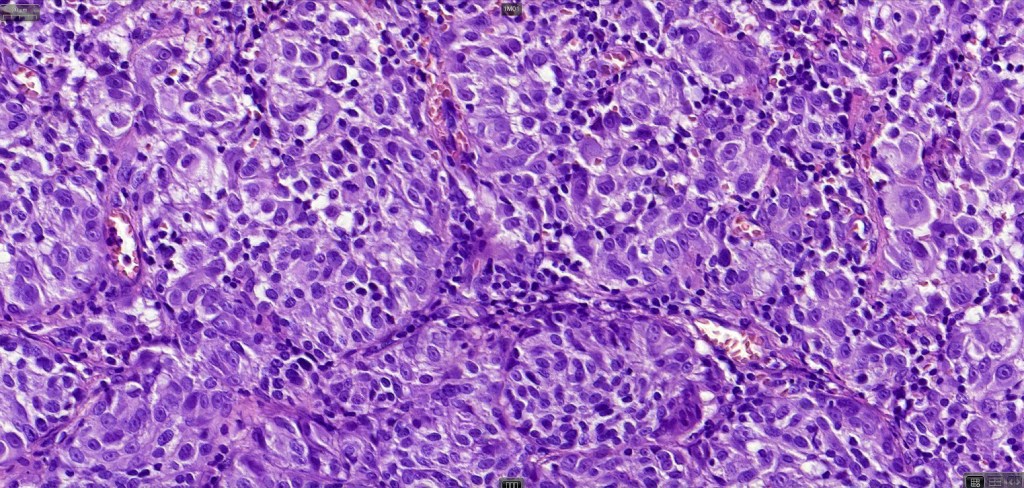

An exceedingly rare variant of melanoma. The term includes cases of melanoma that show features of an associated inherited bullous dermatosis such as epidermolysis bullosa or acquired immunobullous intraepidermal or sub epidermal bullous dermatosis such as pemphigus or bullous pemphigoid and cases where the blister develops directly overlying the melanoma in the absence of any underlying/associated blistering condition. It is generally recommended that measurement of the melanoma should be from taken below the blister/vesicle so as to avoid over-estimating tumor thickness.

Case courtesy of Dr. Antonina Kalmykova